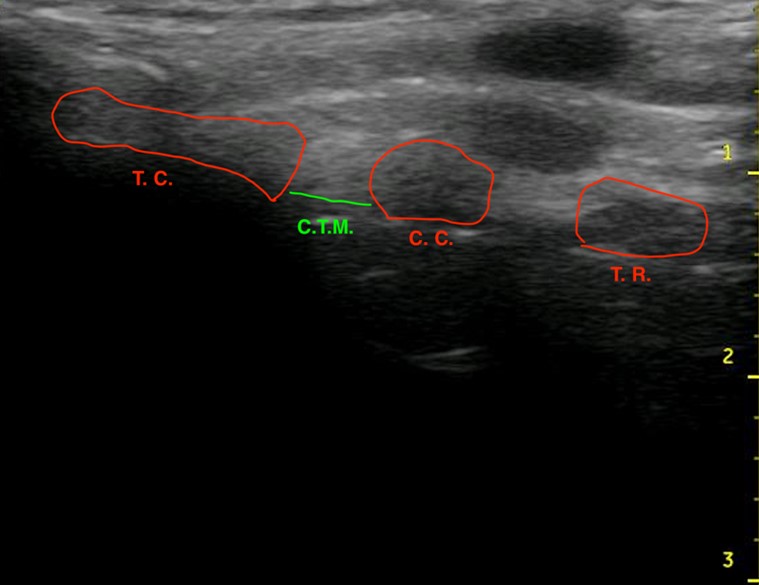

Figure 1.Ultrasound of the midsagittal plane of the anterior neck showing the thyroid cartilage (T.C.), cricothyroid membrane (C.T.M.), cricoid cartilage (C.C.), and the first tracheal ring (T.R.).